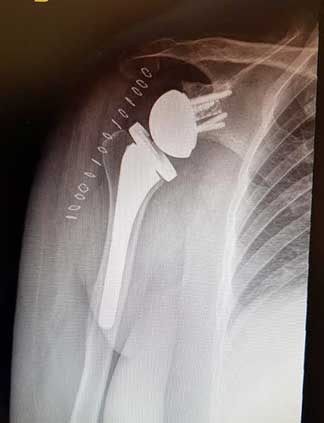

Es la sustitución artificial de la articulación por un implante de metal y polietileno indicada por artrosis, desgaste o lesión masiva del manguito rotador.

La recuperación de la cirugía reemplazo de hombro con una prótesis reversa de hombro o una prótesis anatómica de hombro va muy ligada al estado de la articulación previamente lesionada y al apego que tenga el paciente con la terapia física y así poder ofrecer una recuperación buena, muy buena o excelente.

Radiografía postquirúrgica de prótesis reversa de hombro derecho.